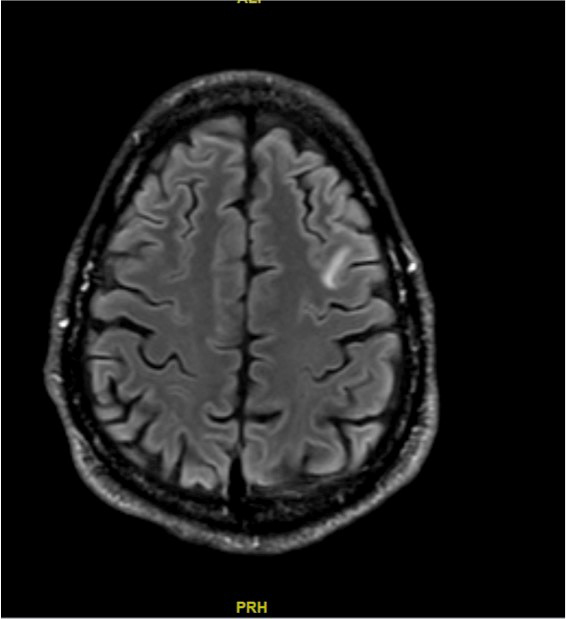

Une IRM est alors réalisée (coupe T2 FLAIR axiales) (images ci-dessous) : Les coupes T1 montrent des lésions hypo-intenses des mêmes territoires, mais aucune lésion ne prend le contraste.

Question 11 - Quel(s) est(sont) le(s) diagnostic(s) retenu(s) à ce stade ?

LEMP : hypo-T1 hyperT2, pas de prise de contraste.

Vous retenez le diagnostic de leucoencéphalopathie multifocale progressive.